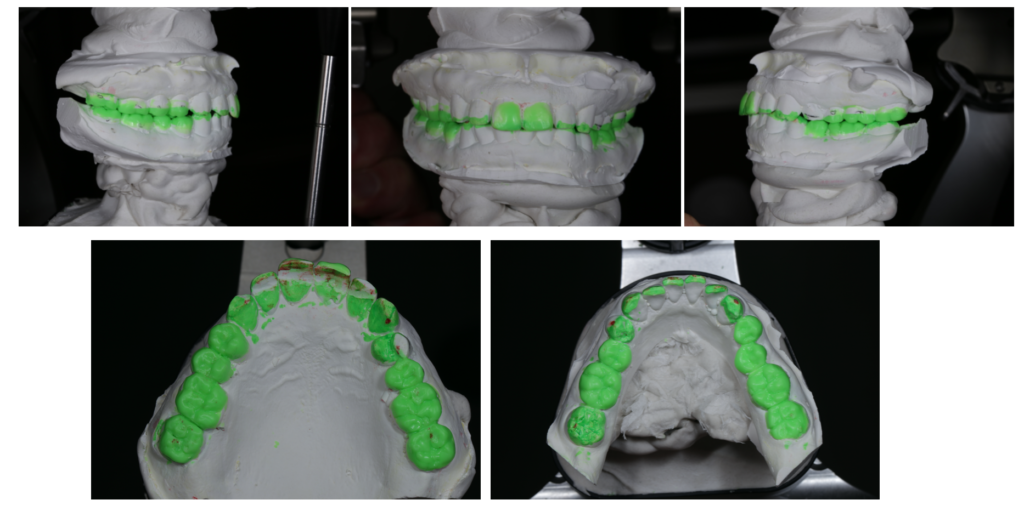

きちんと噛める義歯を作るために欠かせない「リマウント法」という調整

「入れ歯が当たって痛い」「噛むとズレる」「食事をすると疲れる」

こうした不満を抱えながら、「入れ歯ってこんなものだよね」と諦めている方は少なくありません。しかし、それは義歯の限界ではなく、調整方法の問題であることがほとんどで…